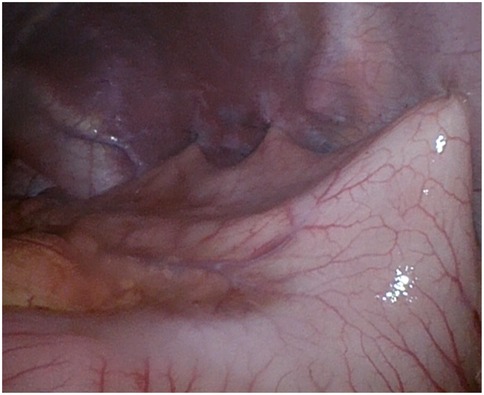

Background Acute gastric volvulus is a rare condition in children, and a delay in diagnosis may lead to gastric ischemia, perforation and even death. It is sometimes associated with wandering spleen, a condition where the spleen migrates from its normal anatomical position due to the absence of fixation ligaments. We report the first case of a patient affected by Pitt-Hopkins syndrome with simultaneous acute gastric volvulus and wandering spleen. Case report A 6-year-old male affected by Pitt-Hopkins syndrome, was urgently referred for acute abdominal pain and 24-hour history of non-bilious and non-bloody emesis. X-ray showed a massive gastric dilatation. Upper gastrointestinal series (UGI) revealed a gastric outlet obstruction. An emergency laparoscopy revealed a gastric mesoaxial volvulus with hypotonic wall with no sign of ischemia or perforation associated with a wondering spleen. Gastropexy was performed by anchoring the gastric greater curvature to the anterior abdominal wall covering the spleen in a good position in the left upper abdomen, completely covered by the gastric fundus. The patient made uneventful recovery and was completely asymptomatic. Conclusion To our knowledge, this is the first case of simultaneous gastric volvulus and wandering spleen in a patient affected by Pitt-Hopkins syndrome. Laparoscopic gastropexy is an easy procedure and combines the advantages of all surgical techniques adopted in previous eras.